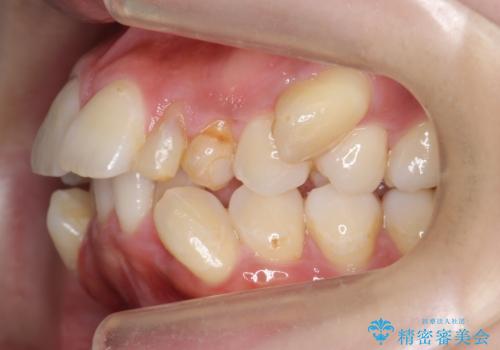

重度のがたつき 矯正治療+セラミック治療で綺麗な歯並びに 矯正専門では難しい治療

- 歯並びを気にして来院。

乳歯が残存しており、また左上の犬歯もずれて生えてきていました。

右上の前歯も細長い特殊な形をしていました。(矮小歯といいます)

左上の奥歯はすれ違っていたためそのかみ合わせも整えています。